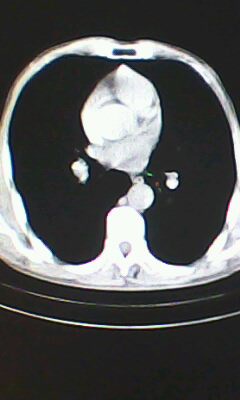

标题: CT26182:男 胸憋 无其它异常症状

胸廓呈桶状,双膈低平,肺实质及纵隔未见明显异常密度灶考虑肺气肿.

肺气肿

以下是引用ctkz987在2010-5-5 21:30:00的发言:[br]胸廓呈桶状,双膈低平,肺实质及纵隔未见明显异常密度灶考虑肺气肿.

弥漫性肺气肿 但内胆管轻度扩张

临床诊断:copd